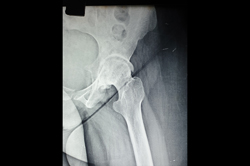

Periprosthetic Fracture THR